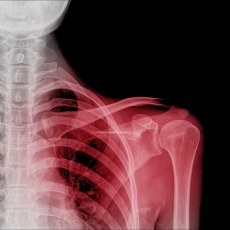

Dislocations are joint injuries that force the ends of your bones out of position. The cause is often a fall or a blow, sometimes from playing a contact sport. You can dislocate your ankles, knees, shoulders, hips, elbows and jaw. You can also dislocate your finger and toe joints. Dislocated joints often are swollen, very painful and visibly out of place. You may not be able to move it.

A dislocated joint is an emergency. If you have one, seek medical attention. Treatment depends on which joint you dislocate and the severity of the injury. It might include manipulations to reposition your bones, medicine, a splint or sling, and rehabilitation. When properly repositioned, a joint will usually function and move normally again in a few weeks. Once you dislocate a shoulder or kneecap, you are more likely to dislocate it again. Wearing protective gear during sports may help prevent dislocations.

Bone X-Ray

(American College of Radiology; Radiological Society of North America)